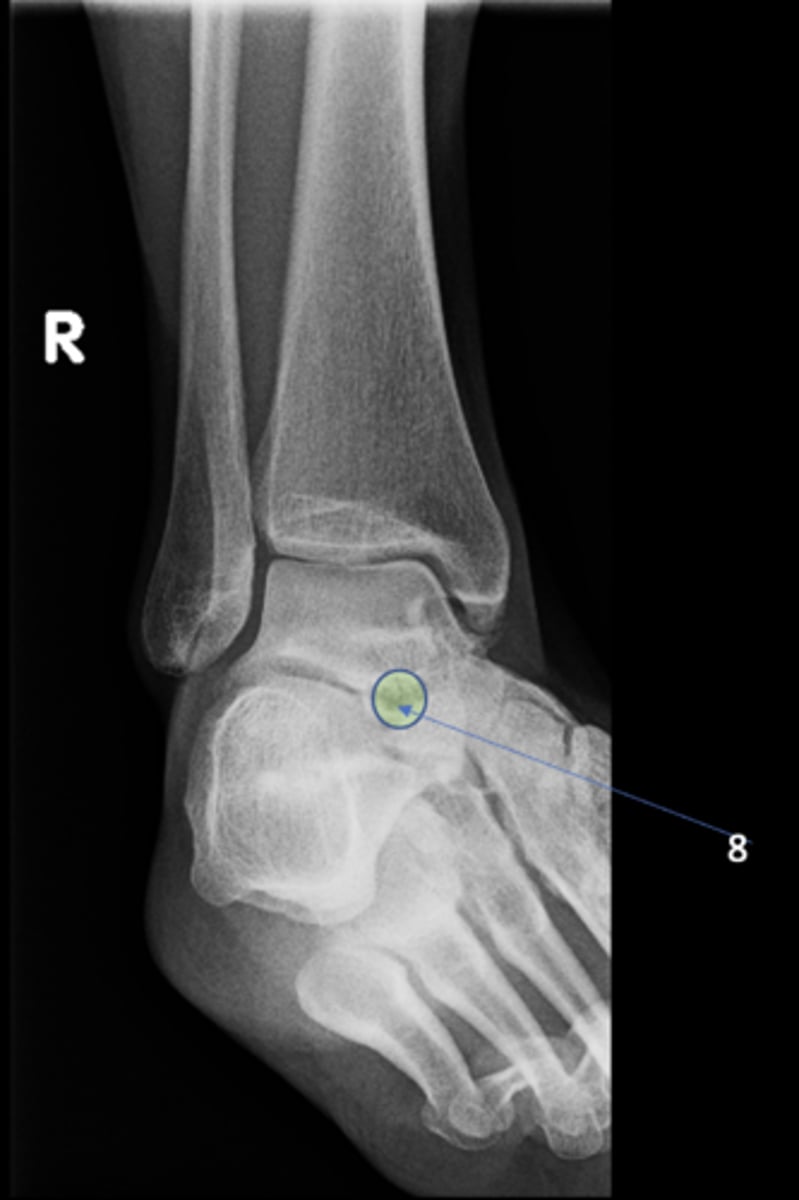

Right medial oblique ankle

View?

<p>View?</p>

<p>ID 12</p>

13

New cards

Left anterior inferior iliac spine

ID 13

<p>ID 13</p>

14

Lateral malleolus

ID 1

Tibial plafond

ID 2

Trochlea of talus

ID 3

Talocalcaneal joint

ID 4 (joint)

Sinus tarsi

ID 8

Base of 5th metatarsal

ID 9

Medial malleolus

ID 10